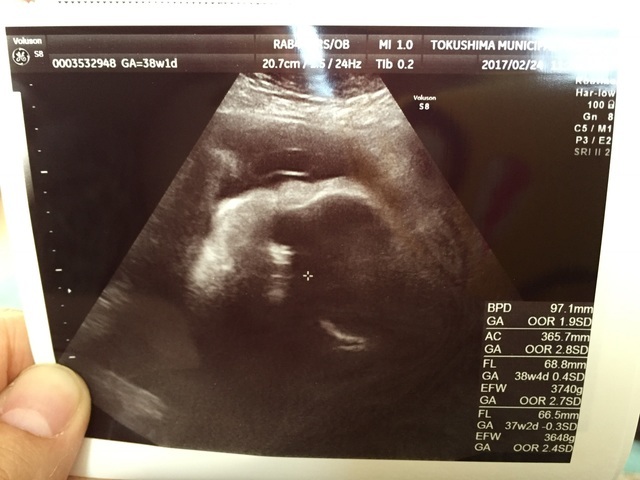

38週1日(38w1d・女の子)|あちゃがしら さん(25歳)

エコー写真撮影時のエピソード:

髪の毛のエコーばっかりでした! 風もないのになびいてますね笑って毎回主治医は笑いながらみてくださいました。

バッチリこっちを向いて微笑んでいる時があって主治医とキャーキャー言いながらとってもらったエコーです